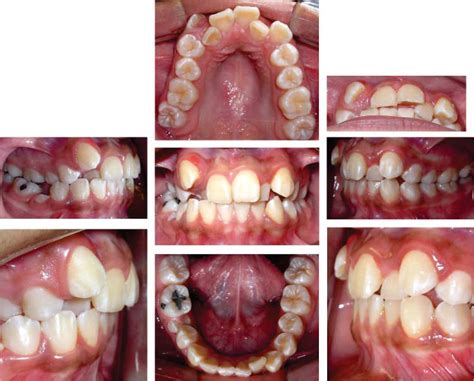

Figura 2 Fotografías intraorales pretratamiento.

Figura 3 Fotografías intraorales pretratamiento. Vista oclusal.

La paciente ya ha iniciado la segunda fase de recambio de la dentición mixta, existiendo caries oclusodistal en 64, origen de un absceso que fistuliza a este nivel por vestibular, posible caries palatina en 26 y oclusomesial a nivel de 74. Ambos primeros molares superiores presentan sendas obturaciones oclusales. La relación molar es de Clase II, completa en el lado derecho e incompleta en el lado izquierdo, estando aumentados el resalte y la sobremordida. La oclusión en relación céntrica mandibular es coincidente con la máxima intercuspidación. Existe una ligera discrepancia de líneas medias, estando la línea media inferior levemente desplazada hacia la derecha con respecto a la superior. Los incisivos superiores aparecen diastemados, intuyéndose una discrepancia oseodentaria positiva en la arcada superior, mientras que, por el contrario, la arcada inferior evidencia una clara discrepancia oseodentaria negativa (figs. 2 y 3).